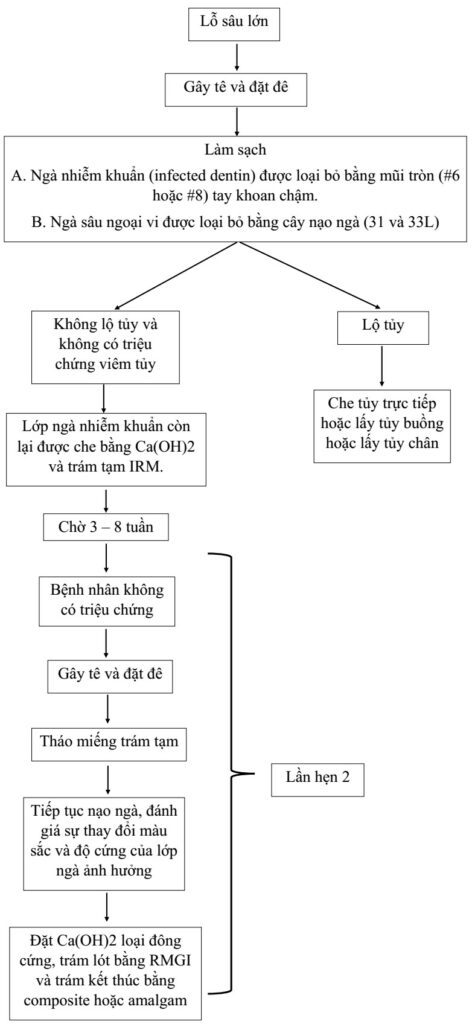

Che tủy gián tiếp có thể thực hiện bằng kĩ thuật 1 thì hoặc 2 thì (hay nạo ngà bậc thang).

Nạo ngà bậc thang (stepwise excavation) là kĩ thuật loại bỏ mô sâu từ từ trong nhiều lần hẹn, có thể trong vòng vài tháng thay vì nạo sạch ngà răng trong một lần.

Kĩ thuật này được chỉ định cho những răng sâu lớn mà không có triệu chứng viêm tủy. Khi thực hiện, ta chỉ nạo ngà mềm vào lần hẹn đầu tiên, sau đó trám lại và lại mở ra sau vài tuần. Tiếp tục nạo ngà vào những lần hẹn sau cho tới khi trám kết thúc.